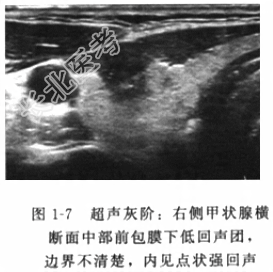

- [材料题] 患者男性,48岁,因“发现右颈部肿块半年”入院。患者自诉于半年前在一次单位的例行体检中发现右颈部一肿块(具体不详),无伴随任何不适,当时未予重视就诊。1个月前自觉肿块增大,遂就诊于我院。发病以来,一般情况尚可,进食和大小便如常,体重无变化。体格检查体温(T)36.1℃,呼吸(R)21次/分,脉搏(P)82次/分,血压(BP)137/88mmHg。神志清楚,表情自然,面色如常,气管无偏移,右颈部甲状腺中极可扪及一直径约蚕豆大小肿块,质地硬,边界不清楚,触痛明显,随吞咽上下移动,未能扪及明显肿大淋巴结。辅助检查血常规、尿常规、粪常规、甲状腺功能(T₃、T₄、FT₃、FT₄、TSH、TG、TG-Ab、TPO-Ab)以及肝肾功能、电解质和血清癌胚抗原(CEA)等肿瘤标志物在内的实验室检验结果未见明显异常。双侧甲状腺超声:右侧甲状腺中部可见一实性肿块,直径约0.8cm,形态不规则,边缘呈毛刺状,内见细小密集的钙化点,颈部可见多个肿大淋巴结,形态不规则,边界不清楚(图1-7,图1-8)。